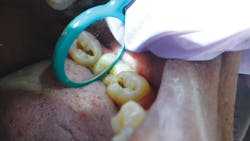

The idea of minimal intervention works perfectly in this setting. Closer to the equator tooth enamel becomes thicker and denser. The decay is different. It can be very aggressive, but usually only on a few teeth. Removing decay early and using a biomimetic glass ionomer such as Triage allows the practitioner to save more teeth. Because IHO works closely with the national health ministry and keeps accurate records, the group can follow the sequelae of the cases and know the results.

Most dentists do not understand glass ionomers. First, they think that the tooth needs to be dry to apply it, particularly in the case of Triage, which is marketed as a sealant. The opposite is true - glass ionomers need moisture to fuse to the tooth. That's what makes it a great material in these situations. Belize has a very humid climate, and keeping teeth dry with mobile equipment is difficult too. The heat and humidity means certain modifications in preparing the material need to be undertaken.. Readying the material needs modification, and shorter mixing times and cooling the capsules works. This gives the practitioner ample time to place the material as a sealant or filling. The material sticks to the tooth much better. The idea of ART (atraumatic restorative treatment) has its roots in glass ionomers. Success of teeth repaired with glass ionomer in conditions where there is no electricity for drills has been proven in many studies. A few studies even looked at the filled teeth up to six years after treatment and found the teeth were still stable.

Glass ionomers have been around for a long time. They lost favor as a restorative material because they're "soft." They don't last long in traditional preps, but they're the perfect material for sealants, cervical decay, and one- or two-surface fillings in primary teeth. They're also useful for people who cannot care for themselves. Combine them with air abrasion and ozone gas, and you have the perfect trio for missionaries intent on saving teeth.

The reason so many teeth are lost in traditional mission trips is because once a tooth is decayed, there's no other way to stop the infection from spreading. In early studies using ozone gas, root decay was reversed with no other treatment than a 10-second exposure of a low concentration of ozone. Results were apparent two years after the application of the gas with no other treatment. Depending on the case presented, disinfecting the minimal prep using ozone and then applying a biomimetic material gives missionary dentists and dental hygienists an option. On the November 2013 trip, missionaries removed fewer than 100 teeth in over 3,000 teeth treated. On the November 2014 trip, only seven of more than 5,000 treated teeth were removed.

Ozone gas and ozonated water are used after cleaning out decay with the air abrasion units. This treatment removes all infective agents and assures the decay won't continue after we leave.

The tooth can then be filled with a restorative glass ionomer material or be sealed with Triage. Because we work so closely with the Belize Health Department, we know how our program is received and how long the glass ionomer restorations last. They last a long time.